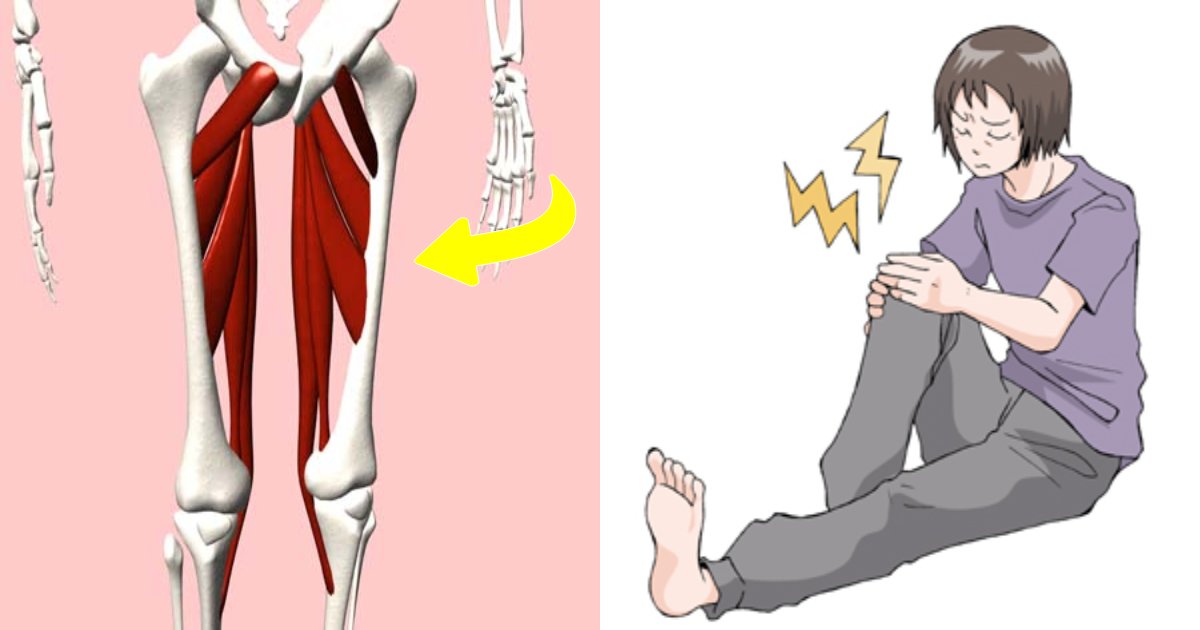

太ももの内側には、大内転筋、長内転筋などの股関節内転筋群という筋肉群があります。内転筋は股関節を内転させる、股を閉じる動きに関わる筋肉で、3層の筋肉層によって構成されています。

第1層(表層)は恥骨筋・薄筋・長内転筋の3つの筋肉があります。第2層(中間層)には短内転筋があります。第3層(深層)には大内転筋・小内転筋があります。これら3つの筋肉を内転筋群と言います。内転筋群に痛みを感じた場合、炎症を起こしている状態は内転筋群炎症になります。

炎症を起こしてしまう原因は色々あります。変形性股関節症、関節リウマチなど病気からくる場合、O脚やX脚など骨格の歪みからくるものになります。腰や足首、足の裏などの痛みをかばうことによっても炎症を起こしてしまうことがあります。症状としては太ももの内側の痛みになりますが、炎症を起こしている筋肉によって痛む場所が変わってきます。太ももの付け根あたりから膝の上あたりまで、筋肉の伸びる部位のどこかで痛みを感じます。